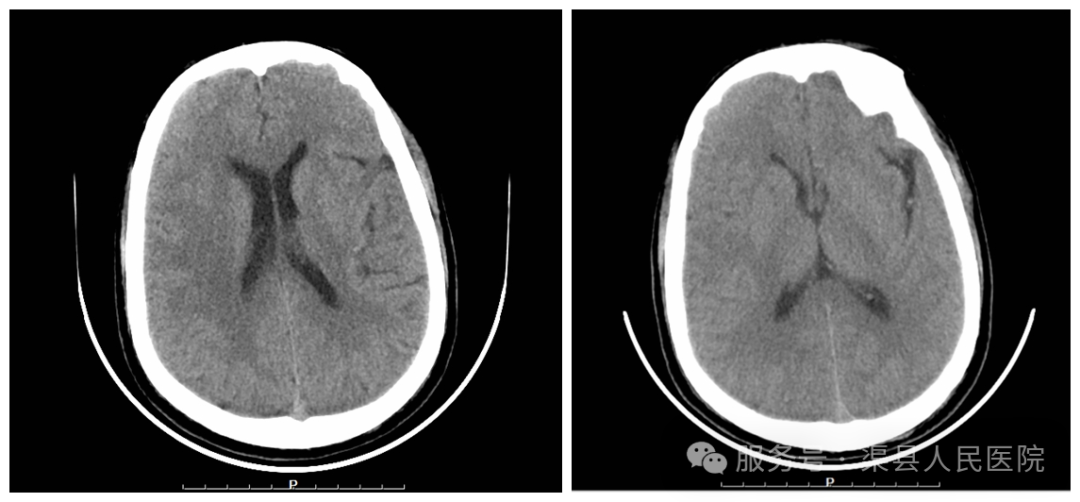

鉴于情况紧急,医院随即启动卒中绿色通道程序。急诊行头颅CT显示无脑出血和低密度影,经科室会诊后决定开展头颅CTP检查(脑组织灌注成像),通过该项检查进行脑组织核心梗死区与缺血半暗带评估。

在影像联合科的全力配合下,即刻得到结果:核心梗死区:0ml,缺血半暗带:23.7ml,Mismatch比值:无穷大。结合患者的抽血结果和《中国急性缺血性卒中诊治指南》(2023版),患者具有静脉溶栓指征,立即于CT室进行溶栓治疗。

患者很快就有好转:说话明显清楚、左侧上下肢的肌力明显好转。24小时后复查头颅CT未见脑出血——本次溶栓成功!7天后患者病情几乎完全恢复,自行办理出院手续并走出医院。